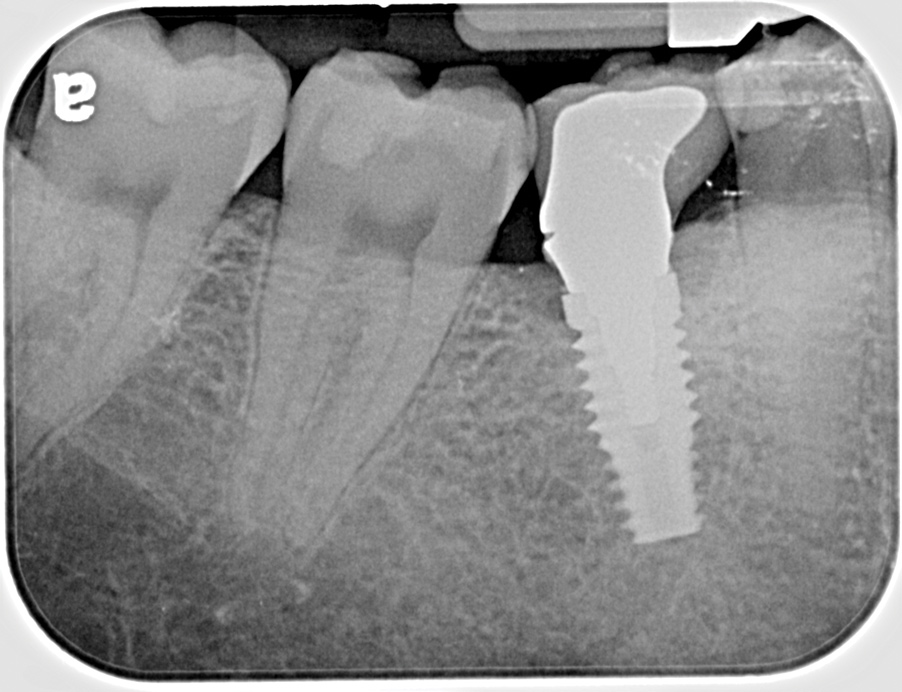

Fig 13. Radiograph depicting peri-implantitis.

Figure 13

Fig 16. Radiograph depicting closed contact at time of implant insertion.

Figure 16

Fig 17. Open proximal contact between implant and adjacent tooth 3 years post insertion.

Figure 17

Excess Cement Leading to Peri-implantitis

If all implant-supported crowns could be designed for screw retention, no discussion of excess cement would be necessary. However, screw retention is not always possible depending on the location of the access opening and because of the unesthetic appearance in anterior restorations or the mesial/distal angulation of the implant compromising the path of insertion (Figure 12). Residual cement left after crown cementation on implants can lead to peri-implant inflammation, peri-implantitis, and eventual loss of the implant (Figure 13 through Figure 15).25 The presence of lingering excess cement can encourage the development of bacterial colonization and peri-implantitis. Conversely, when too little cement is used, voids in the cement layer can occur and the prosthesis can become loose.26 The deeper the implant crown margin, the more difficult it is to remove excess cement.27

Radiopaque cements that contain zinc phosphate and zinc oxide (with and without eugenol) should be considered to help identify excess interproximal cement; however, this should be used secondarily to proper margin height and careful removal of cement during cementation. Resin cements lack the same opacity as zinc-containing cements and have been shown to be the most difficult to remove.28 Often in the process of removing this excess cement, the abutment surface becomes scratched and damaged, potentiating further plaque accumulation.29

Several modifications in abutment design and cementation have been suggested. Placing vent holes in the abutment during fabrication or leaving most of the screw-access chamber open for access has reduced the amount of cement that expresses out into the sulcus.26 It is also beneficial to extraorally express excess cement on an abutment replica prior to final crown seating to minimize complications. If retrievability is desired with cementable implant crowns, weaker cements (eg, zinc oxide eugenol) should be used first and progressively changed until the desired retention is achieved.